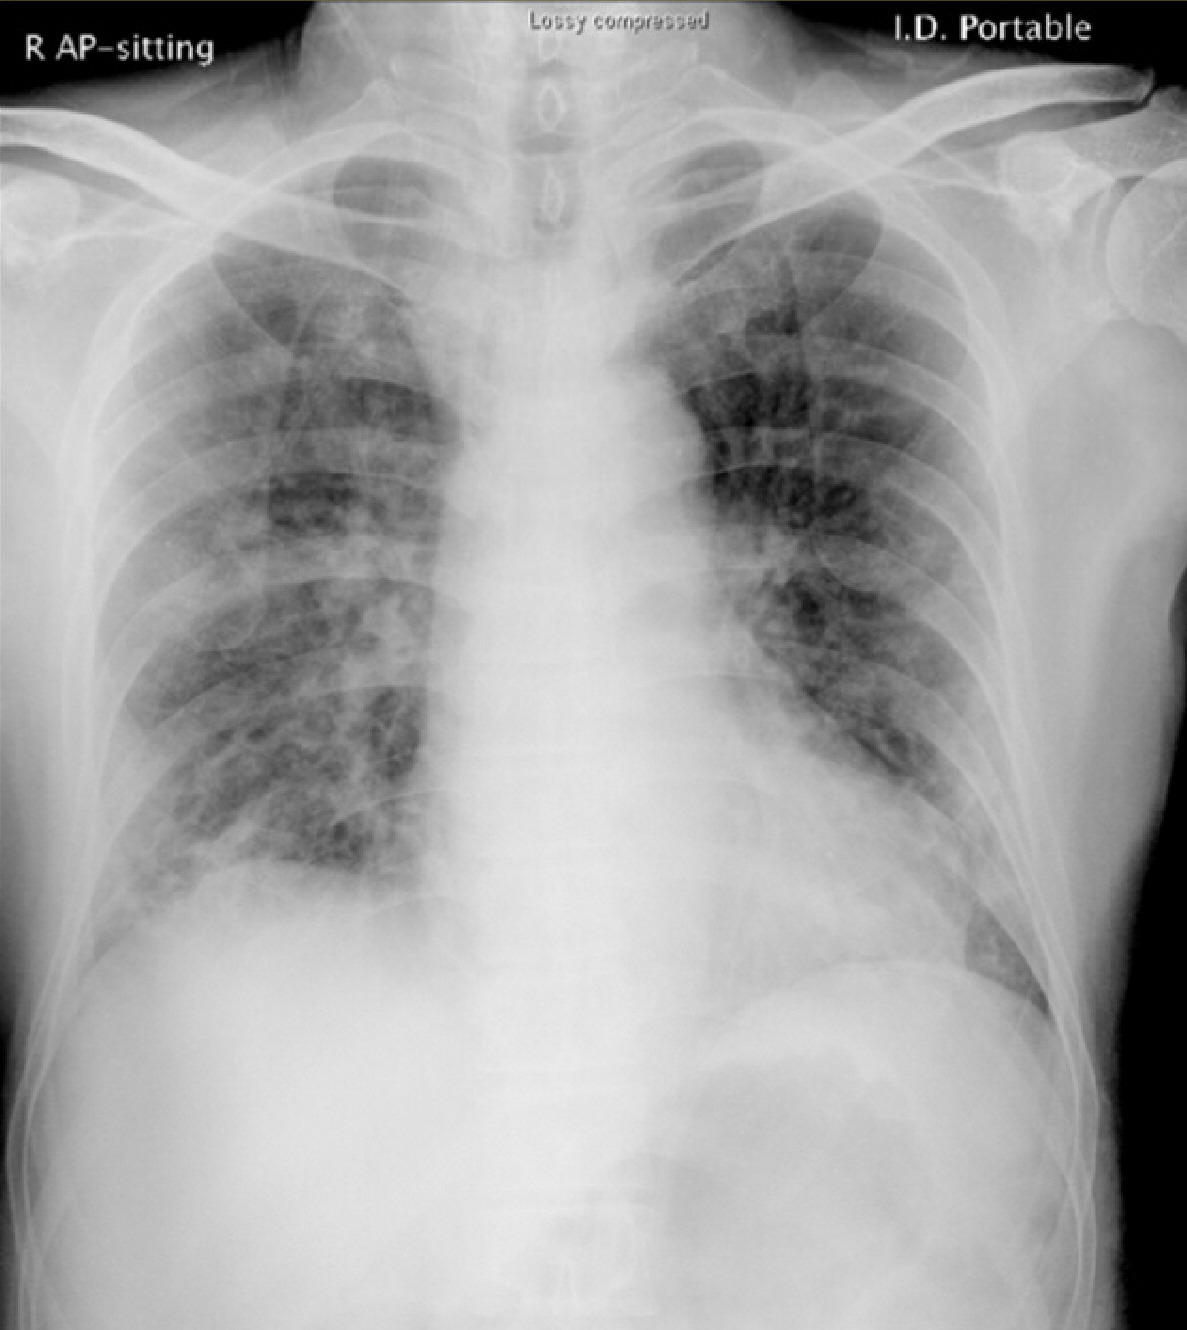

All our experiments use five-fold cross-validation to split target class. To compose the complete test set we use the fold used as a test, together with all the outliers samples. Finally, we repeat the approach twenty times taking means and variance to compare our results with other models. In our experiments we use six numerical datasets from UCI repository (see. Table. 5) and a novel dataset of Covid-19 that contains chest X-ray or CT images of positive/negative patients (see Fig. 1). In order to have the right comparison criterion in Covid-19 dataset, we extract confusion matrix as reported in Tab. 4 and compute the precision metric described in Eqs. 13 and 14. These last measures are needed to compare the class accuracy of the proposed OCdmst and the Resnet18 used in our experiments.

In the third experiment, we demonstrate by experimental results the effectiveness of our model with few data and compare it with a neural network (Resnet18). We simulate the scenario in which we have too few data to deny common neural networks to make right discrimination of different concepts (two classes in our case). Therefore we apply a 2-Fold cross-validation considering all data available from Covid-19 dataset and we extract the deep features for each model trained (Resnet18). All images have been re-scaled to 256x256 pixels and transformed to gray-scale. Learning rate and batch-size are set to 0.001 and 10 respectively. As evaluation metric we do not consider the total accuracy but we evaluate the accuracy for each class (Precision). Then, we use the deep features as input to our OCdmst using the dataset split in the previous step. The results reported in Tab. 2 show the flexibility of our model to operate also with

Resnet18 learned features using cross-entropy loss. As showed in Tab. 2, Resnet18 does not offer right prediction to recognize instances from negative class. This results is reasonable considering we have too few data with negative labels. Even when we used features extracted by Resnet18 to our model, but OCdmst is able to recognize value from both classes and overcome the right prediction also on positive class. The confusion matrix showed in Fig. 7 and accuracies for each class demonstrate the capability of OCdmst to operate also in a scenario with few data, as well as overcome deep neural networks. This last result is plausible because it represents one of the weaknesses of deep models.